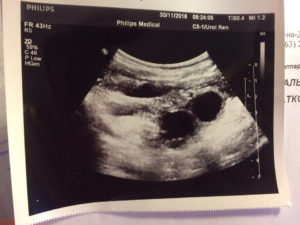

- УЗИ малого таза;

Можно наблюдать многообразные нарушения цикла, месячные часто идут нерегулярно, то задерживаются, то наступают раньше срока. Кровяным выделениям сопутствуют раздражительность, слабость, усталость, головную боль. Для подтверждения диагноза необходимо провести анализ уровня гормонов, провести УЗИ и другие исследования.

Наблюдать рост опухоли может врач на УЗИ. Он же делает выводы о целесообразности лечения.